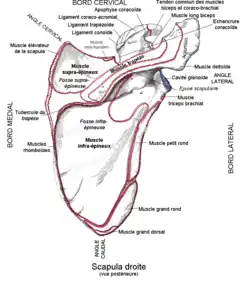

Le chef court du muscle biceps brachial se fixe sur la partie latérale de l'apex du processus coracoïde de la scapula par un tendon commun avec le muscle coraco-brachial.

L'origine du chef long du muscle biceps brachial est intra-capsulaire de l'articulation gléno-humérale et se fixe sur le tubercule supraglénoïdal de la scapula[1] ainsi que sur la partie haute du labrum glénoïdal de la scapula.

Origines scapulaires des deux chefs du muscle biceps brachial.

Origines scapulaires des deux chefs du muscle biceps brachial. Origine du chef long du muscle biceps brachial